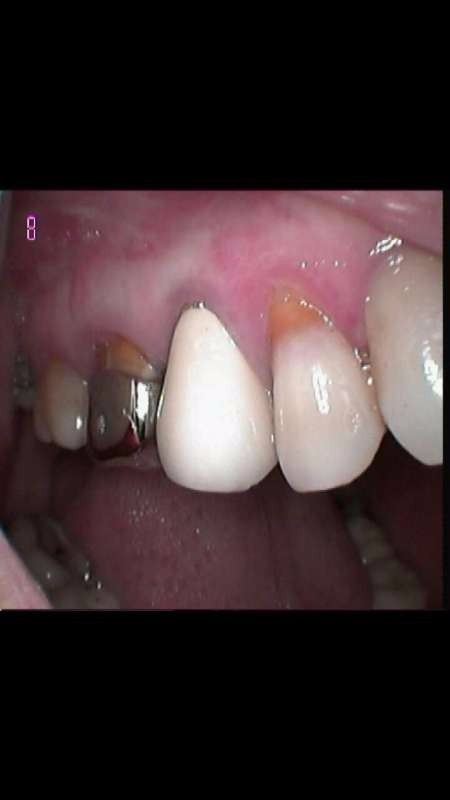

患者45岁,右上5疼痛2周,夜间加重。冷热刺激痛。此牙为烤瓷牙。右上6 钢冠,颈缘露根。拆冠后,根管治疗后56连冠烤瓷修复